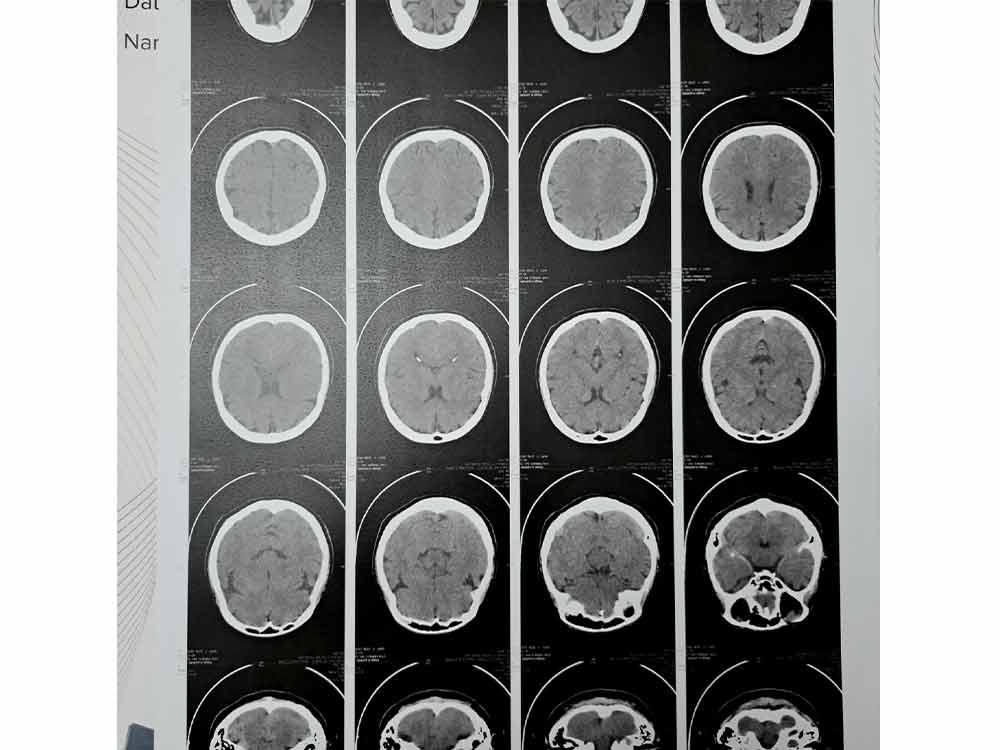

"I thought the end ko na waah, Praise God wala naman hemorrhage but they saw an old clot (chronic infarct) that should've affected my mobility, but they tested me and I am moving okay naman."

After seeking medical attention, the 49-year-old singer-songwriter learned that she had a mini stroke, a temporary blockage of blood flow to the brain.

She revealed, "'Di ko akalain na nagka-minor stroke na pala daw ako nang hindi ko alam. It's a miracle I'm okay. But they needed me to consult a neuro and have an MRI to check and also my ENT.. and so the following days after that there has been a series of doctor check ups and getting clearance from my Ortho doctor.

According to Acel, she still needs to undergo an MRI test to check her head once she's back in the Netherlands as part of her ongoing recuperation and monitoring.